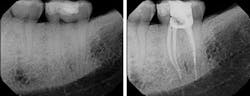

With thermoplastic obturation in its several forms and cold lateral and vertical condensation producing voids and the potential for excess stresses to the roots, my choice for trauma-free obturation is a single-point technique. It is a passive technique that will not generate excessive stresses. The question asked by those using alternate techniques is whether or not it is an effective means for canal obturation. Like all obturation systems, the effectiveness of the single-point technique is based on the cement. However, the single-point technique requires that the cement be an effective seal in both thick and thin layers and that it be present in sufficient quantity that it can fill all the gaps between the master gutta-percha cone and the walls of the canal. For this to happen, we need an instrument that can flood the canal with cement prior to the placement of the prefitted gutta-percha point.

One last question that someone might ask is what do we do when the canals are highly oval with a lot of buccal and lingual space after the master point has been placed? One can go two ways. The cement already flooding the canal is occupying that space effectively and needs no further gutta-percha points. Alternatively, one can use a spreader to create a lateral space for the placement of an auxiliary point with the proviso that the pressure applied to the spreader does not exceed the weight of one’s hand. We have no desire to mold the gutta-percha that would induce the rebound effect or expose the roots to any further stress. Rather, we apply just enough pressure to create a space where a subsequent well-coated point is then placed.

By using a passive obturation technique, we scrupulously avoid the introduction of stresses, maintain the accurate placement of the gutta-percha point, and avoid the introduction of voids that would compromise the seal. The fact that the employment of this technique is simpler and far less expensive is a wonderful marketing feature, but does not surpass the fact that it is safer and kinder to the tooth.